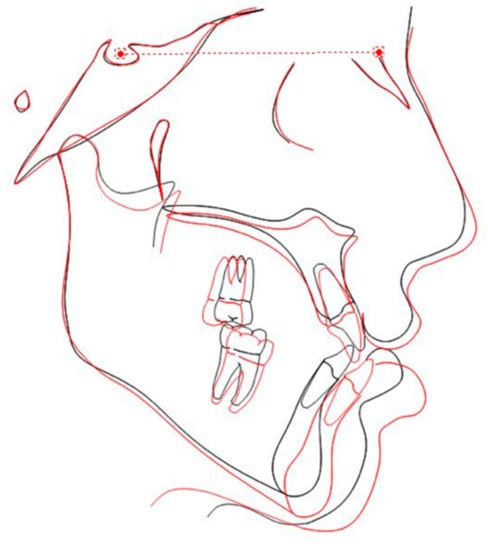

| Variable | Norm | Pretreatment | Post-Treatment |

|---|---|---|---|

| Skeletal | |||

| SNA (°) | 82 | 77.5 | 82.2 |

| SNB (°) | 80 | 82.5 | 82.2 |

| ANB (°) | 2 | −5 | 0 |

| Wits appraisal (mm) | −1 | −9.4 | −3.4 |

| Dental | |||

| Interincisal Angle (U1–L1) (°) | 130 | 124.9 | 112.8 |

| U1–NA (°) | 22 | 30.7 | 36.6 |

| U1–NA (mm) | 4 | 8.4 | 9.9 |

| U1–Mx Base (°) | 110 | 115.8 | 126.8 |

| L1–NB (°) | 25 | 29.4 | 30.5 |

| L1–NB (mm) | 4 | 7.6 | 6.1 |

| L1–GoGn (°) | 92 | 90.3 | 99.1 |

| Soft tissue | |||

| Maxillary lip to E-line (mm) | −2 | −4.3 | −2.5 |

| Mandibular lip to E-line (mm) | 0 | 4.7 | 1.6 |

| Holdaway angle (NB to H-line) (°) | 4.9 | 10.7 |